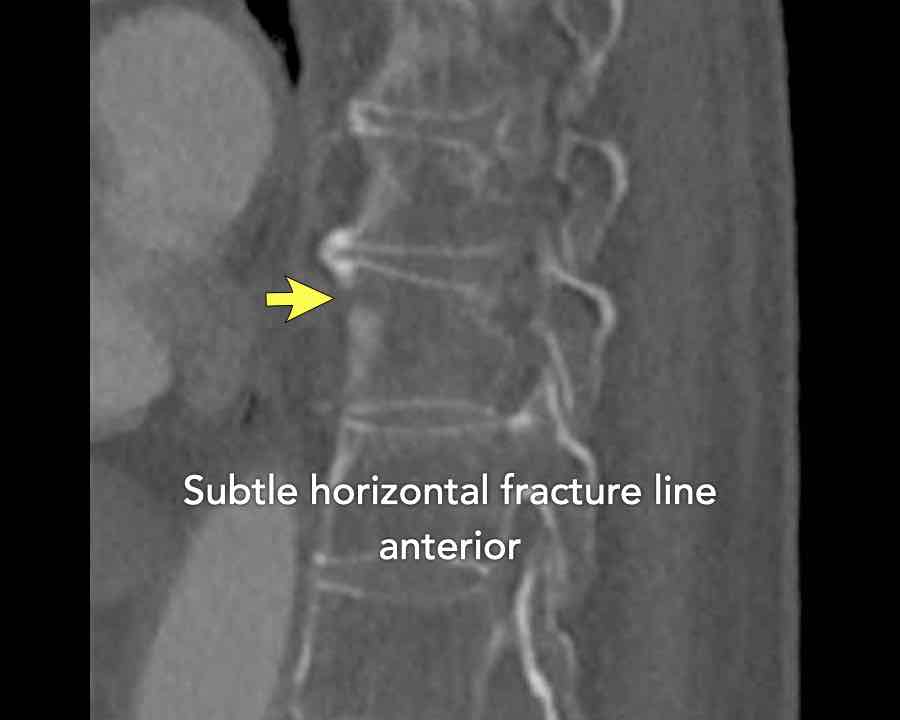

Scroll through images.

What are the findings?

Findings

- C injury? No.

- Signs of a rigid spine?

Yes, so be aware of potentially very subtle B3 injury. - A subtle fracture on the anterior vertebral body is seen (arrows).

Conclusion

Injury type B3.